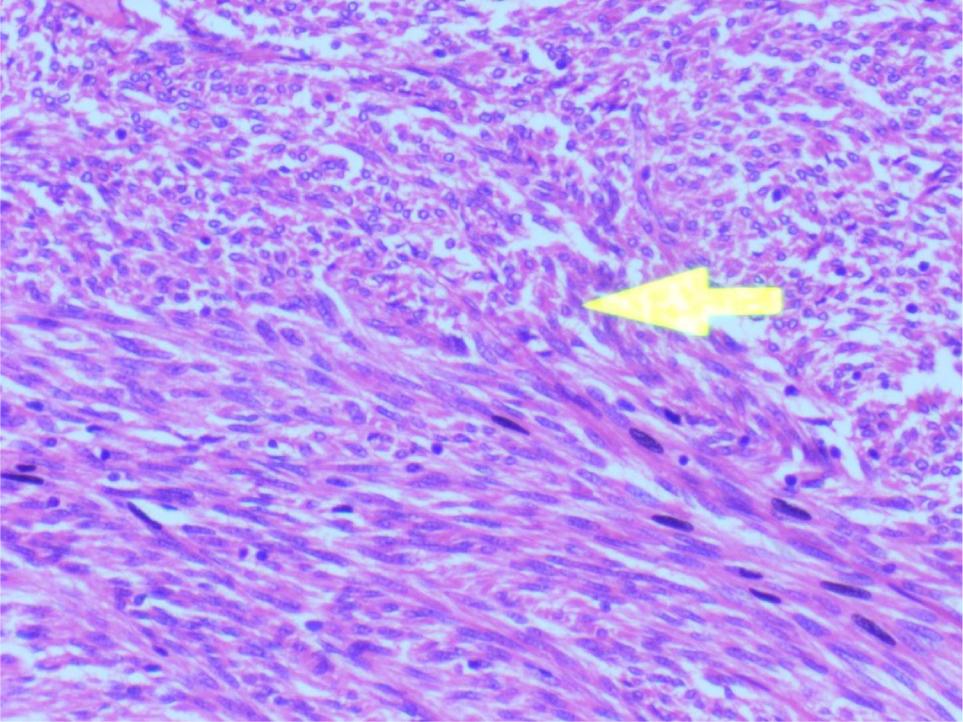

The patient remained hospitalized for 5 days and was discharged 2 days after the surgery. A cut section of the specimen showed tan, white, fragile mass containing hemorrhagic foci. Microscopic examination of sections revealed a lesion composed of haphazardly arranged fascicles and sheets of spindle cells as shown in Figure 3.

Figure 3: Spindle cells showing interlacing pattern. The individual cells have abundant cytoplasm and elongated nuclei with coarse chromatin.

The individual cells have abundant cytoplasm and elongated nuclei with coarse chromatin. Scattered within the lesion are areas of necrosis as shown in Figure 4.

Figure 4: Scattered within the lesion are areas of tumor necrosis seen.